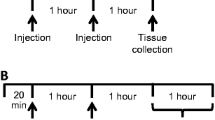

On the following morning (18–22 h after implantation), perfusion began with Dulbecco’s phosphate-buffered saline containing (in milliequivalents): 137 NaCl, 2.7 KCl, 0.5 MgCl2, 1.5 KH2PO4, 8.1 Na2HPO4, 1.2 CaCl2, and 5 % glucose (final pH 7.4). A perfusion rate of 1 μL/min was maintained using a syringe pump (Harvard Apparatus). The perfusate could be changed by switching the perfusion tubing directly at the probe inflow. Given the length of the probe outflow tubing (13.7 cm), there was a lag time of 36.2 min between a change in perfusate and the time at which the new perfusate entered the collection vial. Samples were collected every 30 min until a stable baseline was reached. At that point (t = 0 h), one of the following protocols was followed. In experiment 1, the vehicle perfusate was switched to one containing QUI (0–100 nM, free base). In experiment 2, one group was switched to a perfusate containing the subthreshold concentration of QUI (6.25 nM) while two groups continued to receive the standard perfusate vehicle (VEH). Then, at t = 1 h and t = 2 h, all animals received two identical IP injections of either NAA(−) or a saline VEH (1 ml/280 g). The administration of NAA(−) in two doses at separate time points 60 min apart has been demonstrated to induce a greater degree of TYR depletion than a single administration (McTavish et al. 1999a). The three groups in experiment 2 were: VEH/VEH, VEH/NAA(−), and QUI/NAA(−). Experiment 3 followed the same sequence as experiment 2, except that an additional IP injection of haloperidol (2 ml/kg) was administered at t = 1.5 h. The two groups in experiment 3 were: VEH/VEH/HAL and QUI/NAA(−)/HAL. Data were collected from a single microdialysis session in each rat.

Effect of vehicle (VEH) or quinpirole (QUI) ± a tyrosine- and phenylalanine-free neutral amino acid solution [NAA(−)] on dopamine (DA) levels in a microdialysate. QUI 6.25 nM was administered by reverse dialysis (heavy black line denotes the duration of perfusion) to one of three groups. NAA(−) or VEH was administered IP at the times indicated by the arrows. Results are expressed as percent baseline, with error bars for ±SEM (n = 5/group). Significant differences from vehicle are denoted: *p < 0.05, **p < 0.01, ***p < 0.001 (ANOVA followed by Bonferroni t test comparison to VEH)

Effect of vehicle (VEH) or quinpirole (QUI) ± a tyrosine- and phenylalanine-free neutral amino acid solution [NAA(−)] and haloperidol (HAL) on dopamine (DA) levels in a microdialysate. QUI 6.25 nM was administered by reverse dialysis (heavy black line denotes the duration of perfusion) to one of two groups. NAA(−) or VEH was administered IP at the times indicated by the arrows. Haloperidol (10.0 nmol/kg for MPFC and 0.10 nmol/kg for the striatum; Westerink et al. 2001) was administered IP at the time denoted by the arrow (n = 4/group). There were no significant differences between the groups